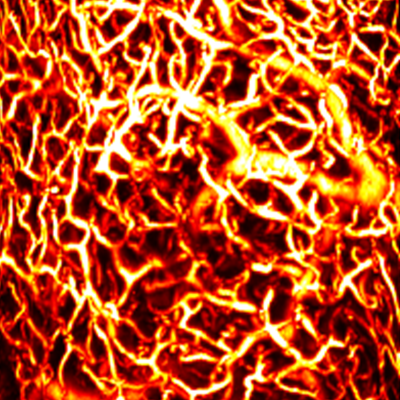

Layer by layer visualization of subdermal microvessels and pigments

MAP